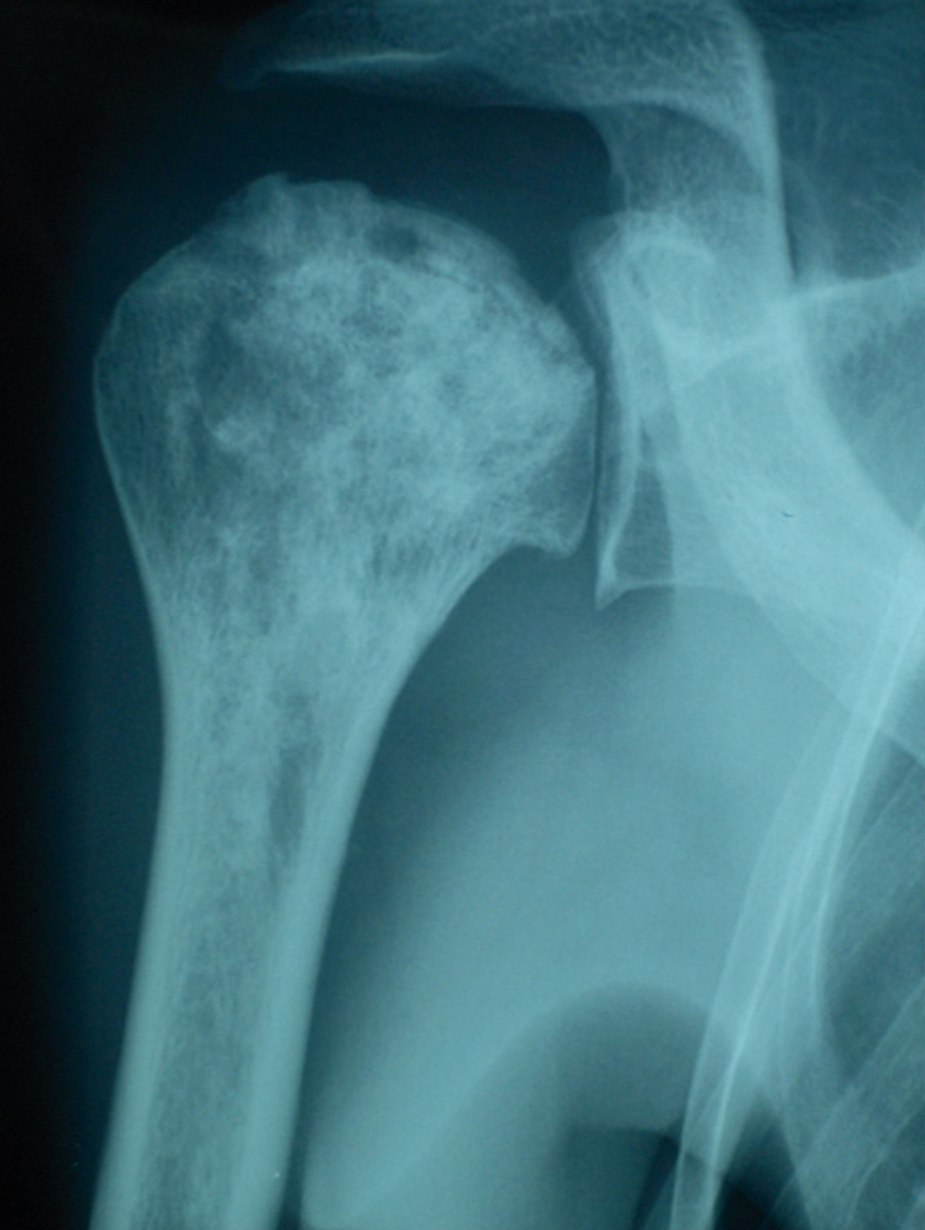

Quel est votre diagnostic ?

Il s'agit d'une ostéonécrose aseptique évoluée de la tête humérale chez un patient drépanocytaire. Les ostéonécroses touchent principalement les têtes fémorales, humérales, et les condyles fémoraux, mais des atteintes peuvent se voir sur d'autres sites. La physiopathologie de ces atteintes est méconnue, mais pourrait impliquer des phénomènes d'adhérence anormale ou d'hyperviscosité. Un patient ayant fait un épisode d'ostéonécrose est à plus haut risque d'avoir une deuxième atteinte qu'un patient qui en est indemne ; les corticoïdes peuvent avoir un rôle déclencheur ou aggravant. Il est important de savoir dépister précocement les ostéonécroses et de les confirmer par l'imagerie par résonance magnétique avant que les lésions ne soient visibles à la radiographie. En effet, un traitement conservateur par ponction-concentration- réinjection de moelle osseuse permet, dans la majorité des cas, de surseoir à une arthroplastie, dont l'indication est toujours délicate à un jeune âge.